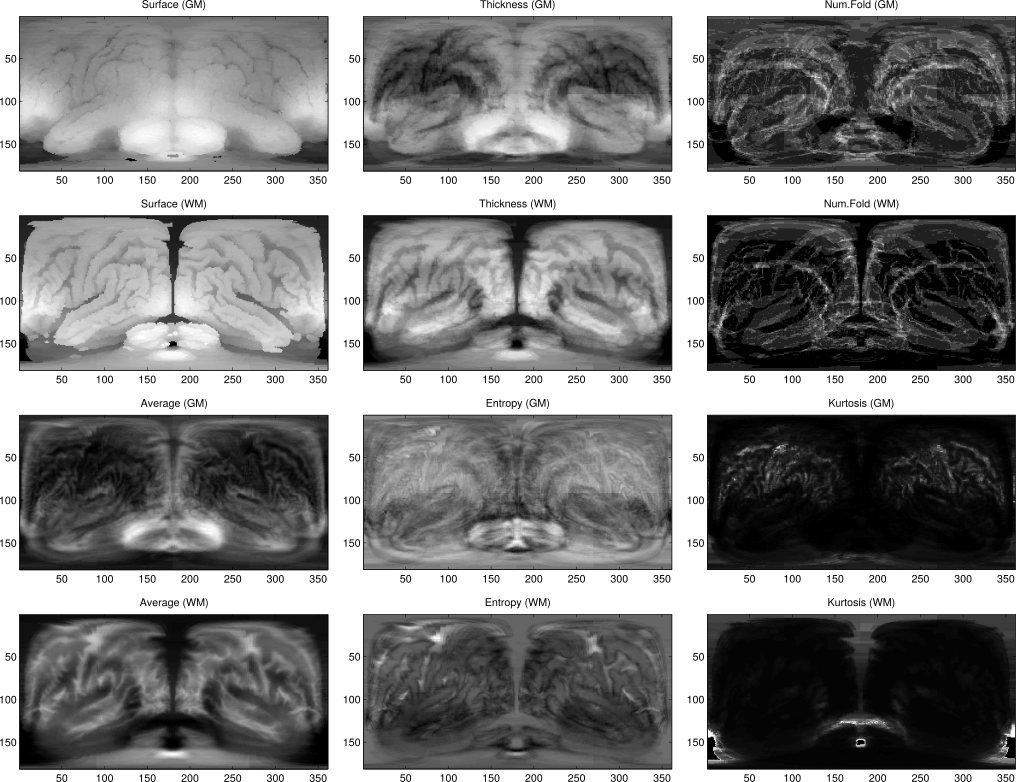

The Spherical Brain Mapping (SBM) is a framework intended to map the internal structures and features of the brain onto a 2D image that summarizes all this information, as described in (F. J. Martinez-Murcia et al. 2016) and previously presented in (F. J. Martinez-Murcia et al. 2014) and (Francisco Jesus Martinez-Murcia et al. 2015). 3D brain imaging, such as MRI or PET produces a huge amount of data that is currently analysed using uni or multivariate approaches.

Spherical Brain Mapping uses an algorithm to perform a projection of the different tissues of the brain to a single plane that can be visually analysed.